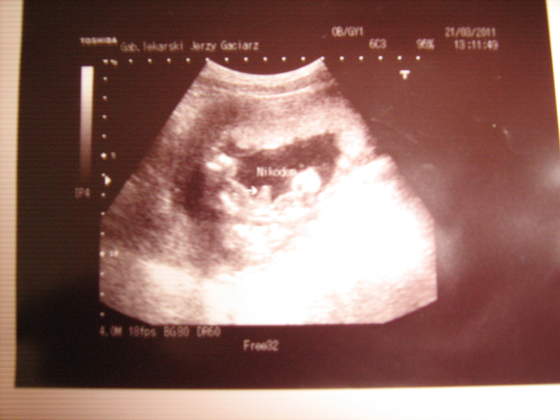

u mnie było tak,że tatuś wypatrzył w 12 tyg siusiaka, ale lekarz powiedział, że też zauważył ale nie chciał nic mówić bo to wcześnie. A potem wszyscy łącznie z tym samym lekarzem mówili, że dziewczynka, dziewczynka ....a urodził się chłopak

Jutro mam 4d, jak potwierdzi mój arabski spec chłopaka to Wam wstawię zdjęcie siusiaka ;-)